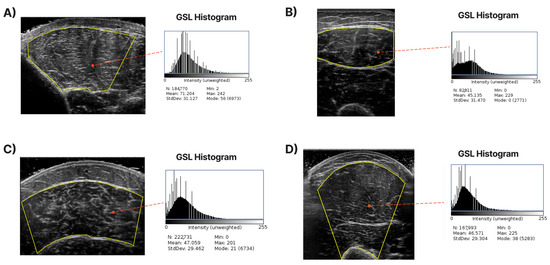

In Figure 1, samples of the studied muscles are presented for normal and high echogenicity images. It is observable in these images that the muscle aponeuroses, especially in the high echogenicity images, are hard to distinguish from the other muscle tissue, making the accurate localisation of the CSA more challenging.

Figure 1.

Sample of ultrasound recordings with normal and high echogenicity. (A,E) shows images from the T.A., (B,F) shows images from the R.F., (C,G) shows images extracted from the GCM, and finally, (D,H) are images of the B.B.